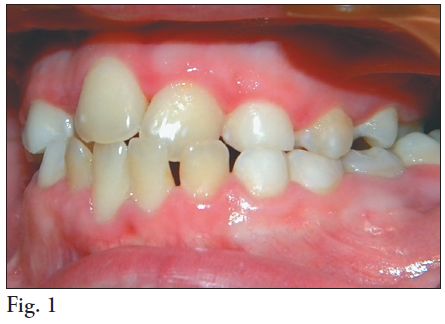

2. MALOCLUSIÓN

Los niños con Síndrome de Down generalmente muestran alteraciones en sus funciones orales tales como protrusión de lengua, succión, masticación y deglución alterada debido a la hipotonía lingual y de los músculos peri orales así como falta de cierre de los labios. Tales alteraciones en sus funciones desencadenan oclusiones traumáticas las cuales junto al bruxismo (frecuente en ellos) (19, 41), favorecen la destrucción periodontal. (21) Es frecuente en estos pacientes las giroversiones dentarias, apiñamientos, mordida abierta anterior y mordida cruzada posterior, siendo (42) la maloclusión dental más frecuente la Clase III de Angle.

(43) En cuanto a la alineación dentaria, adquiere importancia como factor coadyuvante al desarrollo de la enfermedad periodontal ya que dificulta la higiene y ayuda a la retención de placa microbiana, factor desencadenante de la enfermedad periodontal. (Fig. 1)